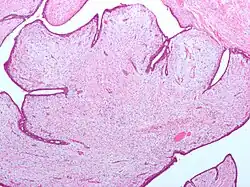

| Fibroepithelial neoplasm (Phyllodes tumor). | |

- Phyllodes tumor of the breast